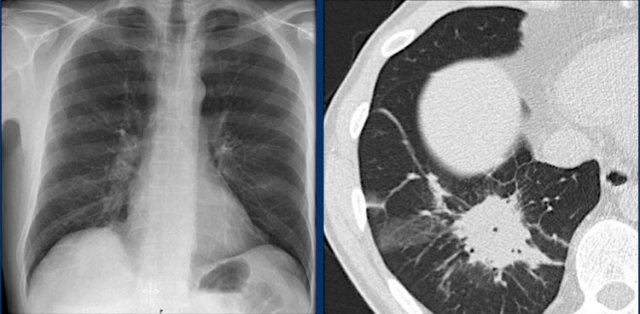

We know that in some cases there is an extra joint in the anterior part of the first rib which may simulate a mass.

However this is also a hidden area where it can be difficult to detect a mass.

In this case a small lung cancer is seen behind the left first rib.

Notice that is is also seen on the lateral view in the retrosternal area.

Continue with the PET-CT.

The PET-CT demonstrates the tumor (arrow) which has already spread to the bone and liver.

The diagnosis was made by a biopsy of an osteeolytic metastasis in the iliac bone.